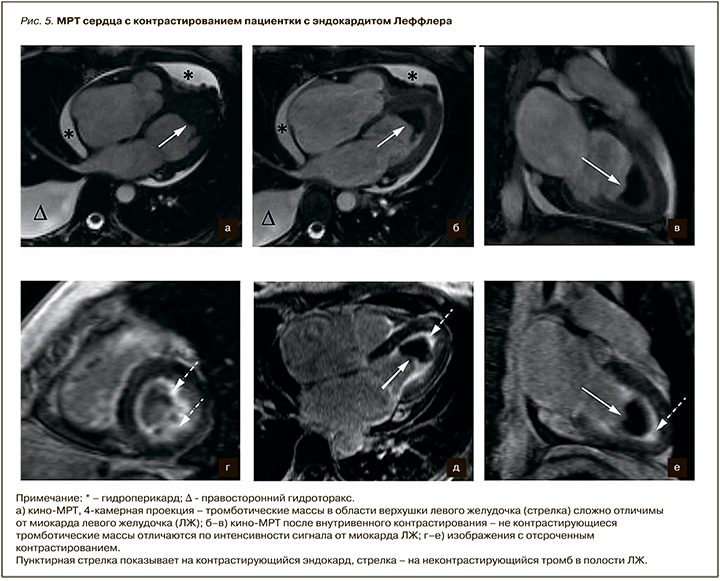

В качестве примера первичной рестриктивной кардиомиопатии можно привести результаты МРТ сердца 42-летней пациентки с эндокардитом Леффлера (рис. 5). У пациентки отмечалась одышка при минимальной физической нагрузке, эпизоды предобморочных состояний, снижение толерантности к физическим нагрузкам. В анализах крови отмечалась эозинофилия (до 16%). При проведении ЭхоКГ был выявлен тромбоз полости ЛЖ, митральная и трикуспидальная регургитация 2 степени, дилатация левого и правого предсердий, умеренное снижение ФВ ЛЖ до 52%, гидроперикард, гидроторакс. При МРТ сердца была подтверждена облитерация верхушки ЛЖ тромбонекротическими массами, признаки эндомиокардиального фиброза ЛЖ.